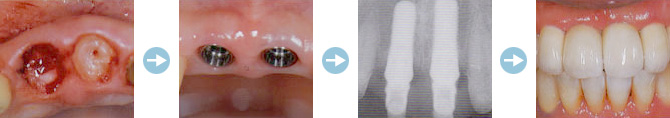

インプラント治療とはチタン製のネジ状のインプラント体(人工歯根:フィクスチャー)を顎骨内に埋め込み、その上に白い人工の歯(上部構造)を装着する治療法です。

インプラント治療の流れ

埋入手術は局所麻酔下で行います。顎骨を露出し、そこにインプラントを埋入し傷を縫合します。

やがてインプラントは周囲の骨と結合し、安定します。

約6~24週間でインプラントは周囲の骨と完全に結合されます。